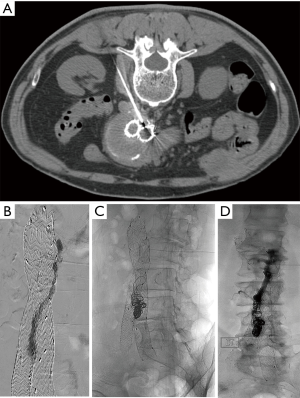

The transarterial approach is the first line of approach at our institutions. When addressing the IMA, a microcatheter is advanced in a retrograde fashion from the SMA via the arc of Riolan or the marginal artery of Drummond to the IMA. When embolizing a lumbar artery, the microcatheter is advanced from the internal iliac artery to the iliolumbar artery to the culprit lumbar artery (Figure 1). In all cases, it is important to advance the microcatheter to the aneurysm sac; however, collateral pathways can be long and tortuous and potentially very difficult or impossible to maneuver. The goal is to completely obliterate the endoleak nidus and eliminate all inflow and outflow vessels. Proximal embolization is not recommended as a type II endoleak will recur by recruiting additional aortic branch vessels.

Some advocate translumbar embolization as the first line of therapy. Ideally, translumbar embolization is performed with combination of CT and fluoroscopy. If CT cannot be utilized, landmarks or cone beam CT may be utilized. The aneurysm sac is accessed at the level the endoleak as demonstrated on CTA. While fusion imaging can be helpful in accessing the proper level, fluoroscopy alone may be used when these more sophisticated technologies are not available. The operator will observe pulsatile blood once the aneurysm sac is successfully accessed. A baseline pressure should be recorded. A diagnostic angiogram or a “saccogram” is performed via a sheath needle to delineate the endoleak cavity and inflow and outflow vessels. A microcatheter is typically advanced to the nidus and attempt to embolize all inflow and outflow vessels as well as the nidus is performed. If there is difficulty addressing all inflow and outflow vessels, EVOH or cyanoacrylate glue may be utilized to embolize the nidus and vessels (Figure 2). A final intrasac pressure should be obtained at the conclusion of embolization.